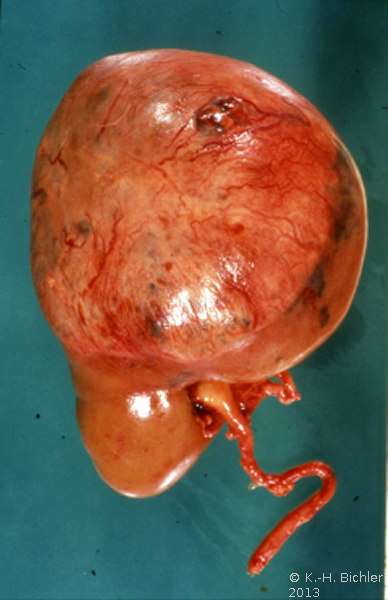

Makroskopisch zeigt der Tumor eine gelborange Farbe und ist durch Einblutungen und weißliche, Nekroseherde gesprenkelt. Außerdem finden sich Zysten von Millimeter- bis Centimeter-Größe (Abbildung 1). Auffällig häufig enthält das Nierentumorgewebe Kalzifizierungen. Zumeist ist der Tumor mehr oder weniger gekapselt und dadurch vom Nierenparenchym abgetrennt (s. Abbildungen Kasuistiken).